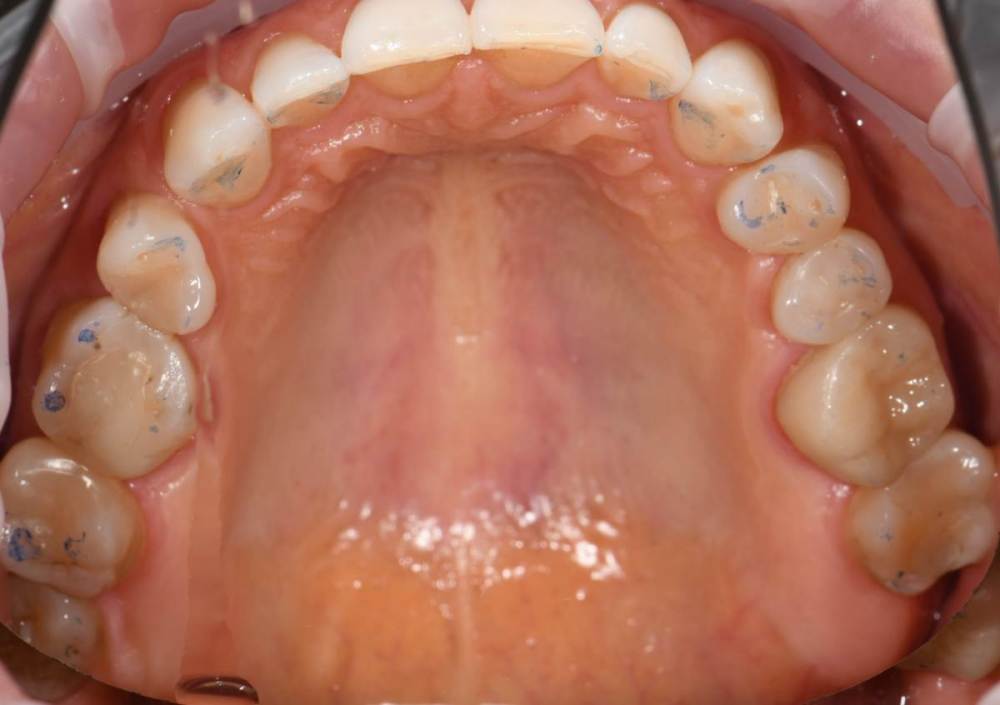

Высылаю фото отпечатков при прикусе , мою искривленную улыбку  панараму 2016 года до имплантации и сейчас. Так же ситуацию с 36.37

DSC_2179.JPG

DSC_2178.JPG

IMG_3345.jpg

IMG_3330.jpg

IMG_3321.JPG